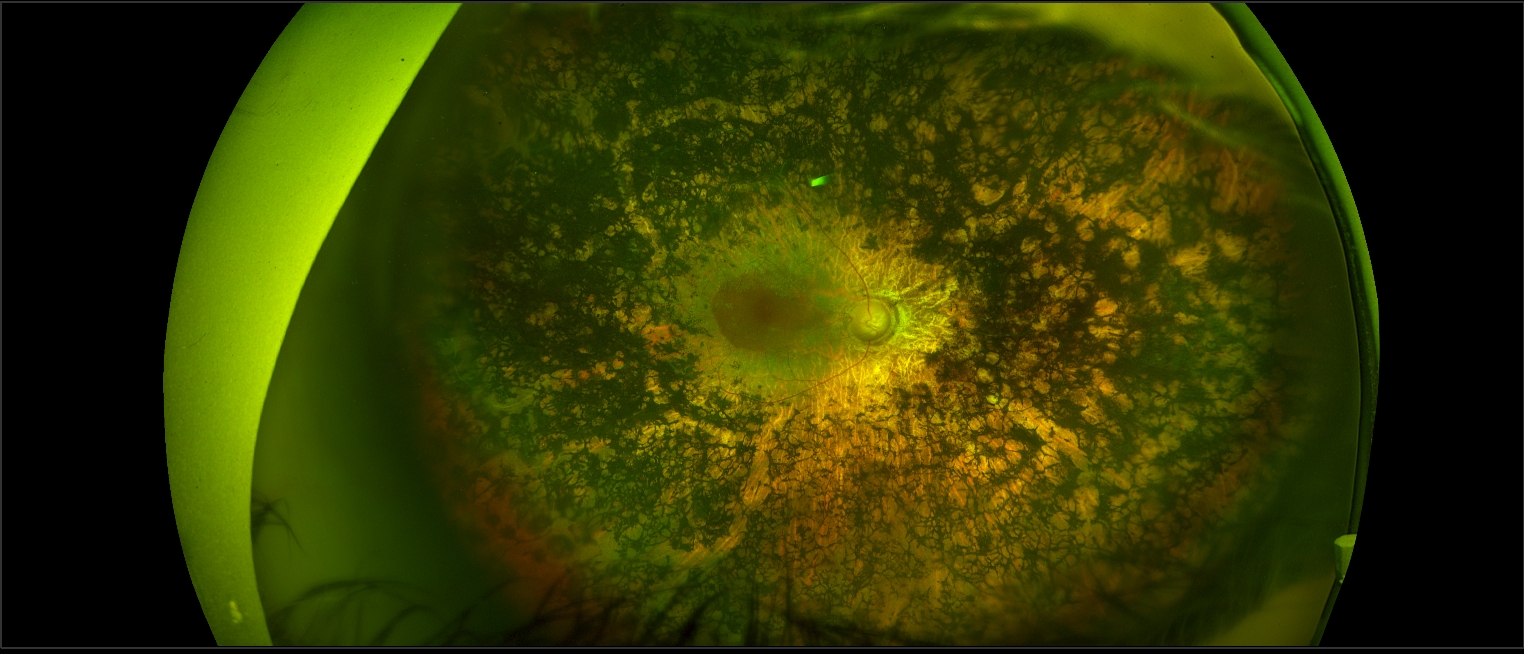

Eye genetics and inherited retinal diseases

We investigate the genetic causes of blinding eye diseases to improve diagnosis and develop new treatments. With an international reputation in inherited retinal diseases (IRDs) such as retinitis pigmentosa, Stargardt disease, cone-rod dystrophies, and macular dystrophies, we are committed to advancing ocular gene therapy.

Inherited retinal diseases (IRDs) are a major cause of vision loss in working-age adults, affecting more than two million people globally.

These disorders are genetically heterogeneous and often slowly progressive, which presents both diagnostic and therapeutic challenges.

Our research focuses on detailed phenotyping, genetic analysis, stem cell-derived retinal models, and development of clinical biomarkers to better understand these conditions and support emerging therapies. Functional testing and multimodal imaging are key tools in evaluating disease progression, informing clinical trial readiness, and guiding precision care.